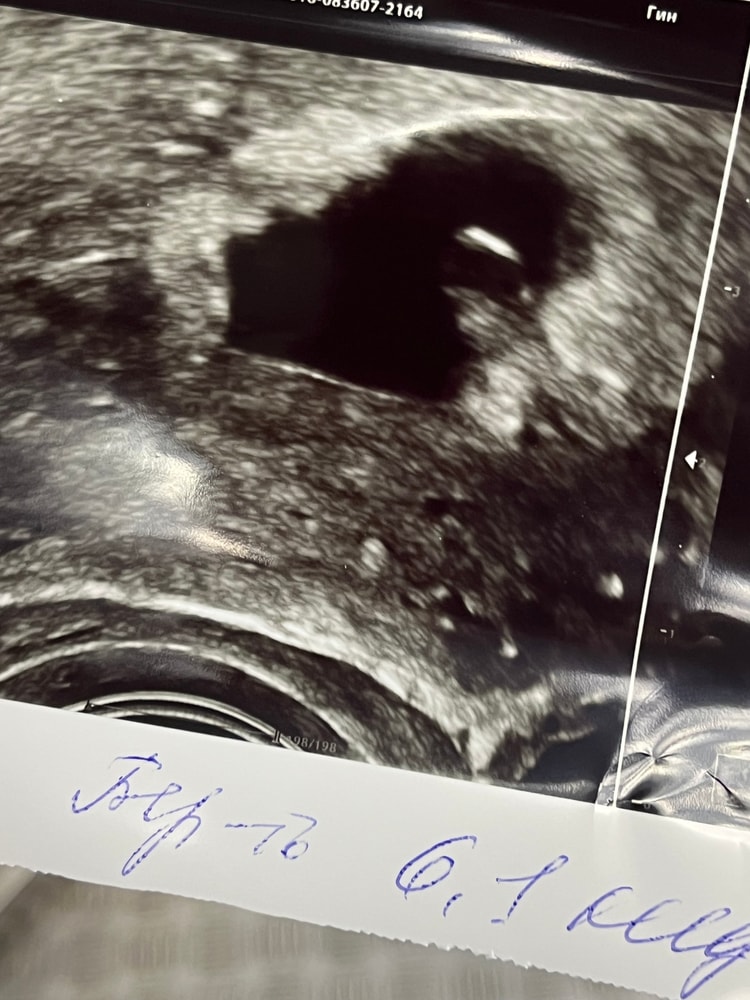

Сходила на узи

Результаты: УЗИ, КТГ, доплера, скринингаТолько что приехала, срок по узи 6 недель и 1 день, эмбриончик один. Был бы милый пост с фото узишки и «ждем малыша», но муж стал на говно исходиться что не хочет больше детей и гонит убирать. Что делать? 🫤 а малыш хорошенький, сердечко бьется, жалко пипец